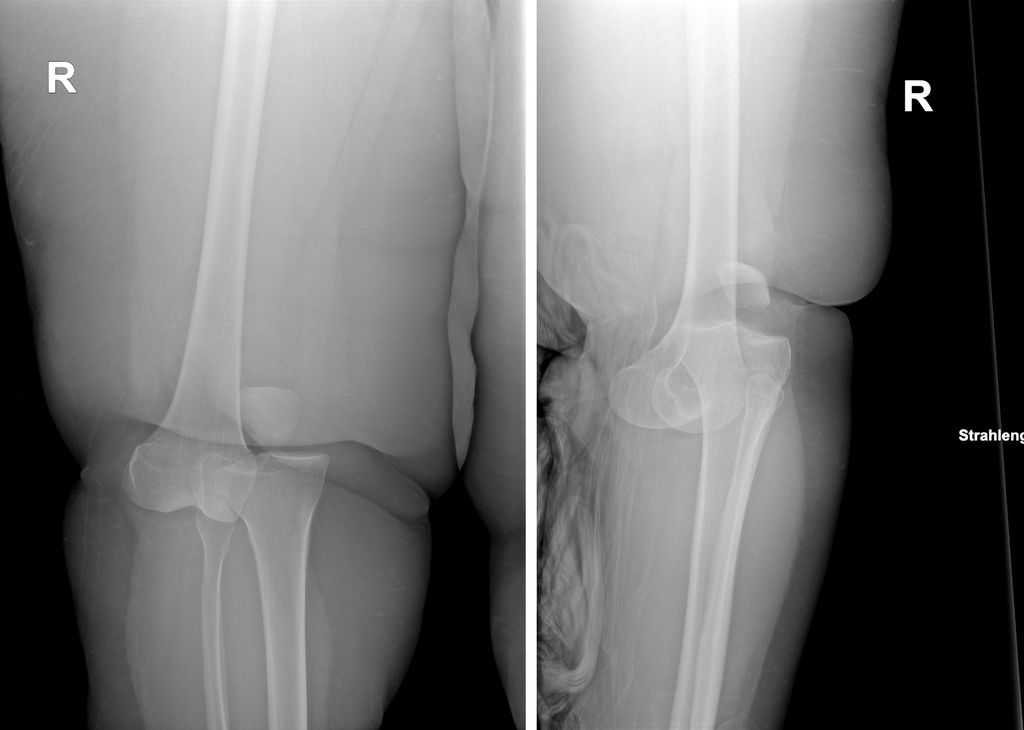

Abb. 1: Röntgenbild einer anterolateralen Knieluxation bei einem „Ultra low energy“-Trauma; links die a.p. Aufnahme, rechts die sagittale Aufnahme

Knieluxationen sind häufig Folge von Hochrasanztraumata mit direktem Anprall gegen das Knie, wie sie z.B. im Rahmen von „dashboard injuries“ bei Verkehrsunfällen, bei Stürzen aus großer Höhe oder bei Sportverletzungen mit enormer Krafteinwirkung vorkommen. Aufgrund des höheren Risikoprofils sind bei diesen Verletzungen vor allem junge Männer im Alter von 18–25 Jahren betroffen. Das Verhältnis zwischen Männern und Frauen in dieser Gruppe beträgt 4:1. Demgegenüber stehen sog. „Ultra low energy“- oder „Ultra low velocity“-Traumata, bei denen stark übergewichtige Patienten eine Kniegelenksluxation erleiden (Abb.1). So reichen aufgrund der Adipositas bereits Bagatelltraumata im Alltag aus, schwerwiegende Verletzungen des Kapsel-Band-Apparates des Kniegelenks zu verursachen.4